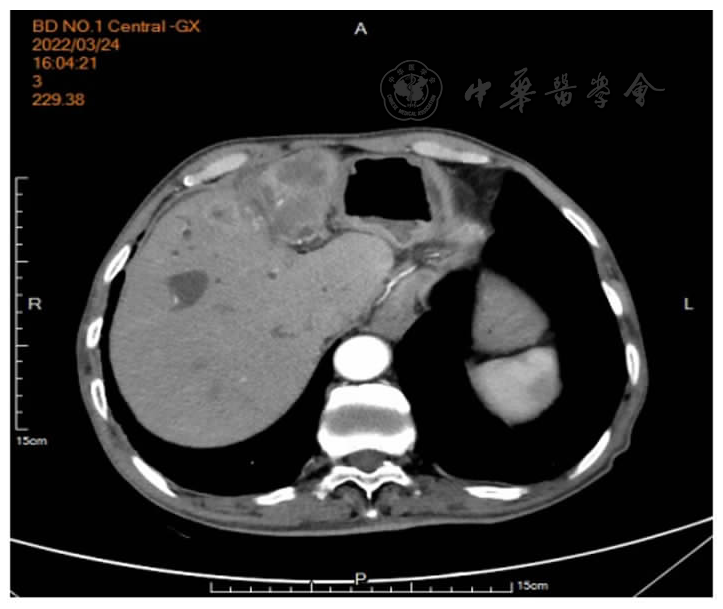

患者男,71岁。主因"右上腹痛伴黄疸1月"于2022年3月11日收入保定市第一中心医院消化内三科。患者1月前无明显诱因出现右上腹部疼痛,呈持续性钝痛,并向肩背部放射,伴发热,体温维持在37.8℃左右,以午后为重,伴寒战、皮肤及小便发黄、偶有恶心、无呕吐、体重下降约2.5 kg。既往19年前因"胆管结石"行"胆总管切开取石及胆道镜下肝内胆管取石术";1年前又因"胆囊结石"行"胆囊切除术"。入院查体:T 37.6℃、P 70次/分、R 17次/分、BP 120/80 mmHg,神志清楚、精神差、结膜无苍白、巩膜黄染、周身浅表淋巴结未触及肿大、心肺查体无异常、腹平软、上腹部可见手术疤痕,有压痛、无反跳痛及肌紧张、肝脾肋下未触及、肝区叩击痛阳性、移动性浊音阴性、肠鸣音正常。入院后辅助检查:血常规:白细胞7.70×109/L、血红蛋白117.00 g/L、血小板226.00×109/L、中性粒细胞比率72.20%;肝功:丙氨酸氨基转移酶46.60 U/L、天门冬氨酸氨基转移酶41.10 U/L、白蛋白36.90 g/L、总胆红素52.60 μmol /L、直接胆红素36.00 μmol/L、间接胆红素16.60 μmol/L、γ-谷氨酰转肽酶620.00 U/L、碱性磷酸酶337.20 U/L;肿瘤标记物:AFP 2.02 ng/ml、CEA 1.62 ng/ml、CA-19927.26 IU/ml;门诊上腹部CT提示:肝左叶体积小;胆总管下段高密度影,结石?考虑低位胆道梗阻。初步诊断:胆总管结石伴化脓性胆管炎。给予抗感染、保肝、抑酸、补液等支持治疗。于2022年3月14日经内镜中心行经内镜逆行胰胆管造影术(endoscopic retrograde cholangiopancreatography,ERCP)取石,术中泛影葡胺造影可见胆总管扩张1.2 cm,下端约见1.0 cm充盈缺损影,胆总管上段不规则充盈缺损影,肝内胆管未见异常,弓形电刀沿乳头11点方向切开约0.3 cm,1.2 cm扩张球囊扩张乳头,取石网篮取出黄褐色结石及黄白色脓性分泌物(图1),术后置入鼻胆引流管,胆汁引流通畅。术后给予暂禁食水、抑酸、补液等综合治疗。患者仍感腹痛,体温最高达38℃,术后第3天复查腹部CT示:ERCP术后改变,肝内胆管扩张;肝顶稍低密度。当时考虑患者腹痛为鼻胆管刺激所致,遂予拔除。复查血常规及肝功能较术前无明显变化,C反应蛋白:37.30 mg/L、血淀粉酶及脂肪酶正常,考虑胆管内感染脓液引流不畅,于3月21日再次行ERCP术:术中胆管造影仍提示胆总管内不规则充盈缺损影,用取石球囊取出大量黄白色脓性分泌物(图2),术毕置入8.5Fr-8 cm塑料胆管支架(图3)。术后患者腹痛仍不能缓解,并出现持续高热,体温最高达38.9℃,抗生素升级为比阿培南0.3 g,12 h 1次静脉点滴。同时口服熊去氧胆酸胶囊250 mg,每日3次,监测肝功能及炎症指标。3月24日行上腹增强CT示:肝顶多发异常强化,考虑肝脓肿可能(图6)。因治疗效果不佳,请感染性疾病科会诊后仍建议继续抗感染治疗,监测炎症指标及脓肿影像学变化,尽可能穿刺引流以缩短病程,并留取血培养以明确致病菌。遂调整比阿培南0.3 g,8 h 1次、加用莫西沙星0.4 g,每日1次联合抗感染,同时加用人血白蛋白支持对症治疗。患者腹痛及发热症状仍无明显缓解,3月31日进行上腹MRI平扫+增强检查提示为肝内多发异常信号,肝内外胆管及胆总管扩张,肝门区胆管截断,肝门区淋巴结肿大(图7)。复查腹部彩超提示肝脓肿,液化不明显,不易穿刺。于2022年4月6日加用去甲万古霉素抗感染治疗,患者治疗效果欠佳。再次请普外科会诊,仔细阅片考虑肝门区胆管截断,肝内多发不均低密度,不除外恶性肿瘤可能,建议穿刺活检。超声造影提示肝内不均质回声,倾向炎性病变,因周边血管丰富穿刺出血风险高,不宜进行穿刺活检。此时患者内科保守治疗效果不佳,恶性肿瘤不能除外,经与患者及家属反复沟通,建议手术治疗,于4月4日转入普外科并行手术探查,术中发现肝左叶萎缩、质硬,多发肿物突出肝表面,右肝未见明显肿物,腹腔广泛粘连,肝门部多发肿大淋巴结,术后病理证实为左半肝低分化胆管细胞癌(图8)。患者术后腹痛好转,体温恢复正常,家属拒绝进一步治疗,自动出院,离院后1个月病逝。

图6 3月24日上腹部增强CT:肝内外胆管扩张,肝顶多发异常强化